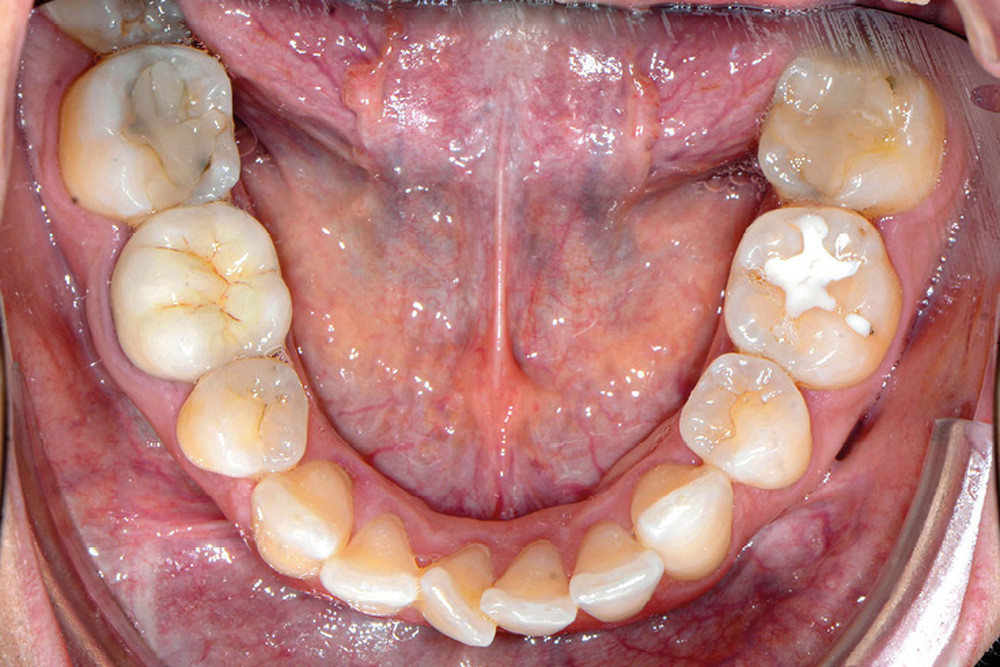

C’est précisément le cas de cette patiente de 33 ans qui présente une classe II squelettique par rétrognathie mandibulaire sur un schéma vertical hyperdivergent associée à une classe II/1 dentaire avec DDA par excès et biproalvéolie. Son profil est convexe, cis-frontal et, sur le plan fonctionnel, on peut observer une dysfonction linguale et une incompétence labiale au repos. Il en résulte une contracture des muscles de la sphère péri-orale lèvres jointes. La formule dentaire n’est pas complète puisque les quatre deuxièmes prémolaires ont été extraites lors d’un premier traitement orthodontique et qu’il y a également agénésie des troisièmes molaires 18 et 38 (fig 1 à 11).